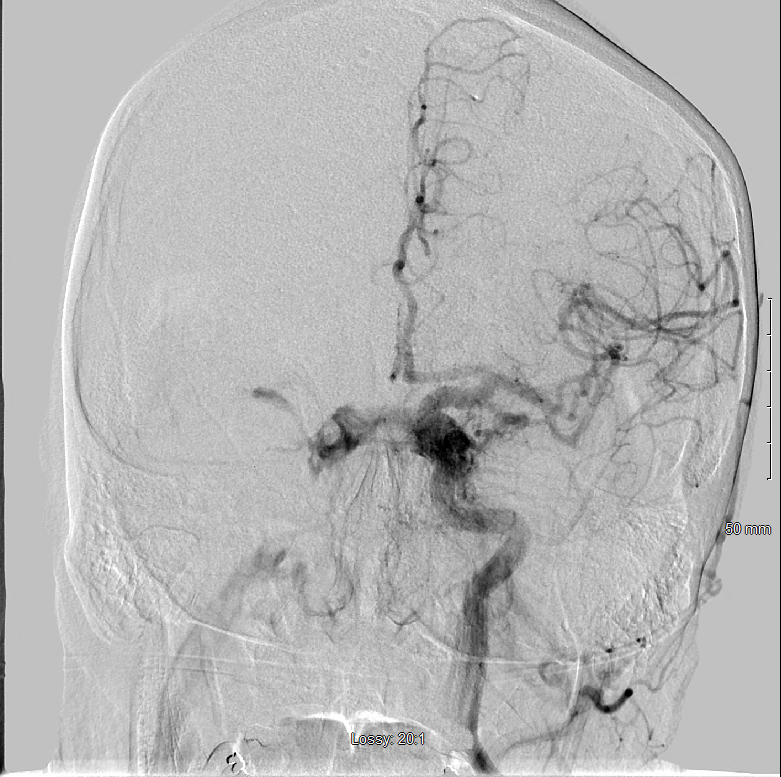

Cerebral angiography was performed, the results of which showed bilateral carotid cavernous fistulas (CCFs) supplied by both the external and internal carotid arteries (Figure 2). Right and left common carotid injection showed numerous arterial feeders arising from the internal maxillary, ascending pharyngeal, and posterior auricular arteries that were supplying the cavernous sinus (CVS). The cerebral angiogram also revealed multiple branches arising from the cavernous and petrous segments of the internal carotid artery, contributing to the fistula.

Figure 2.

Repeated cerebral angiography showed extensive communication between the external and internal carotid arteries and the CVS, consistent with an indirect CCF draining into the right inferior petrosal sinus and superficial ophthalmic vein. The CCF was additionally noted to be draining into the contralateral CVS.